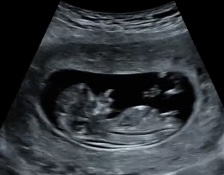

Узи 11 недель

По бугорку прям девочка!

И мне кажется, что девочка ❤️ Обычно когда рано, бугорок ещё в непонятном положении, ни туда, ни сюда. А у вас лежит параллельно. Главное, что здоровый, конечно.

Пол ребенка Скрининг в 13,5 недель в МедЭксперт.